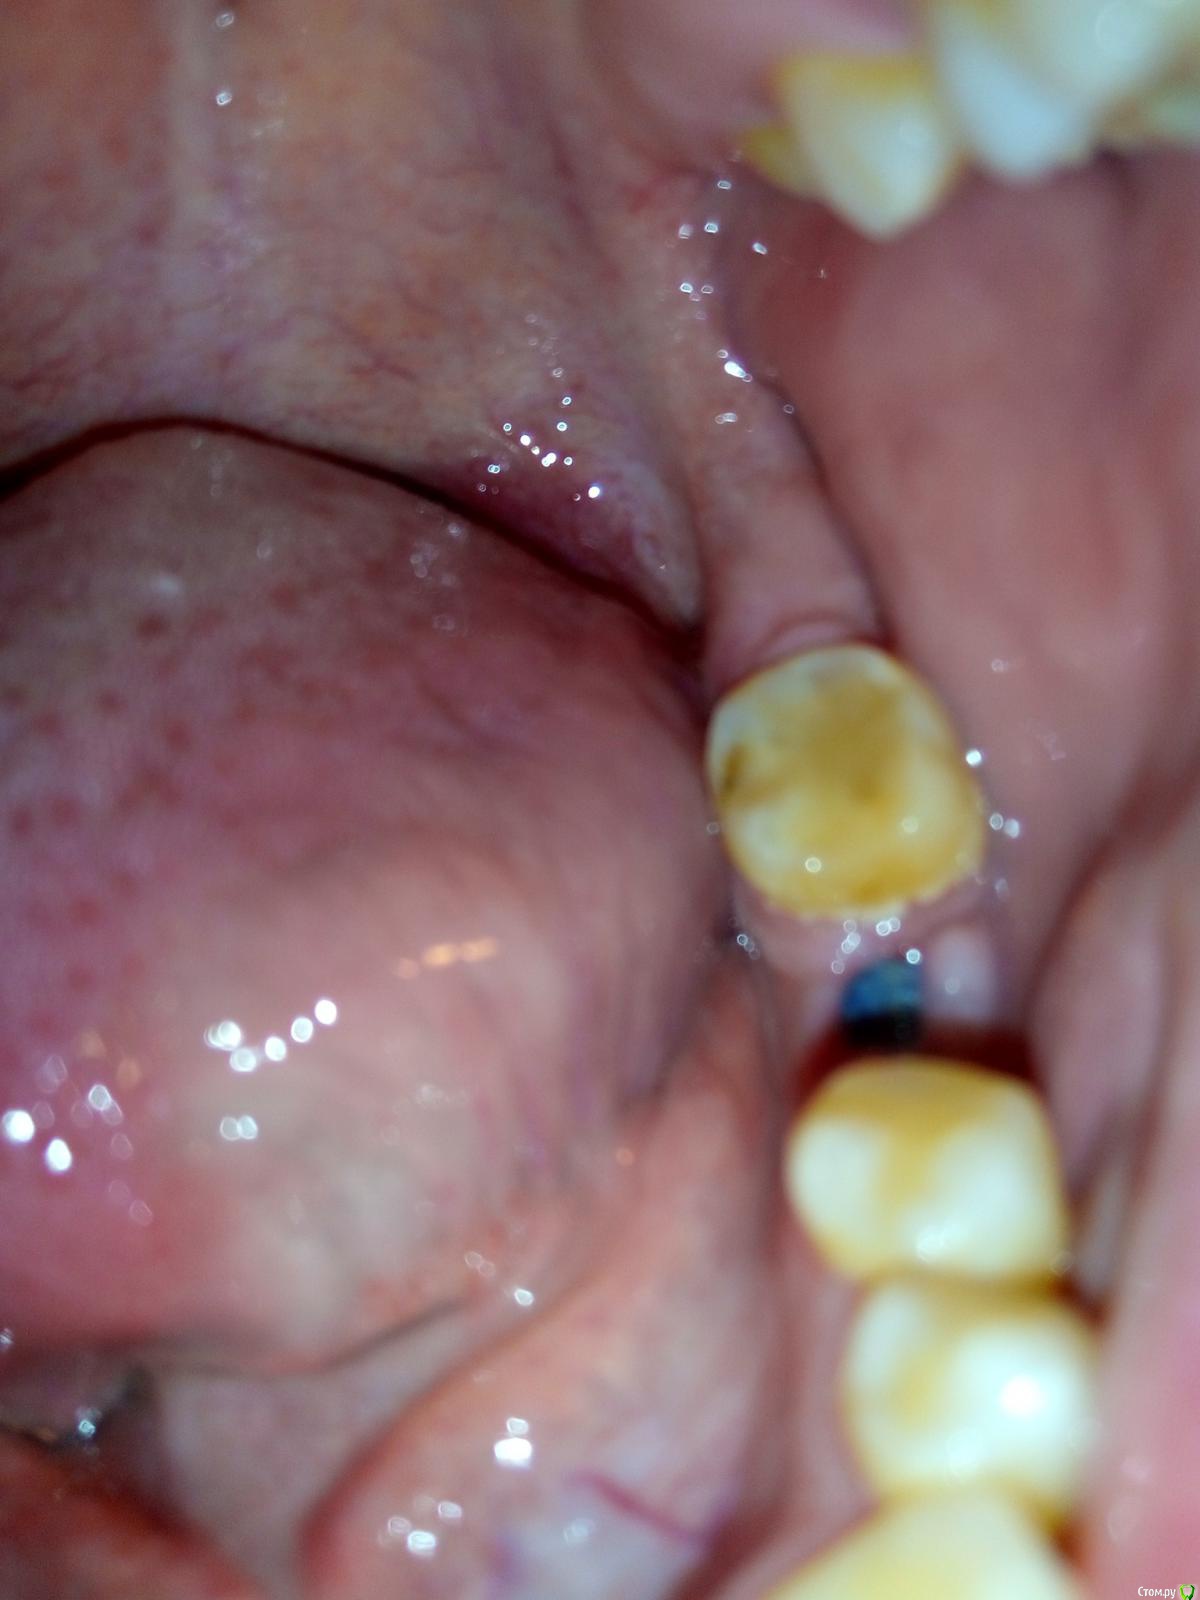

Katyanya Опубликовано 5 января, 2016 Поделиться Опубликовано 5 января, 2016 здравствуйте, нахожусь в другом городе, к зубному через 2 недели. Неделю назад сняли швы, виден имплант. Мне грозит еще раз наложение швов? Чем сейчас мазать чтоб десна быстрее сошлась? Спасибо Ссылка на комментарий

Katyanya Опубликовано 5 января, 2016 Автор Поделиться Опубликовано 5 января, 2016 (изменено) Часть десны со стороны щеки закрывает имплант а другая часть десны открыта Изменено 5 января, 2016 пользователем Katyanya Ссылка на комментарий

diesel87 Опубликовано 5 января, 2016 Поделиться Опубликовано 5 января, 2016 Если ничего не беспокоит, то просто проводим антисептику в области импланта, хлоргексидин ванночки и планово к своему доку. 1 Ссылка на комментарий